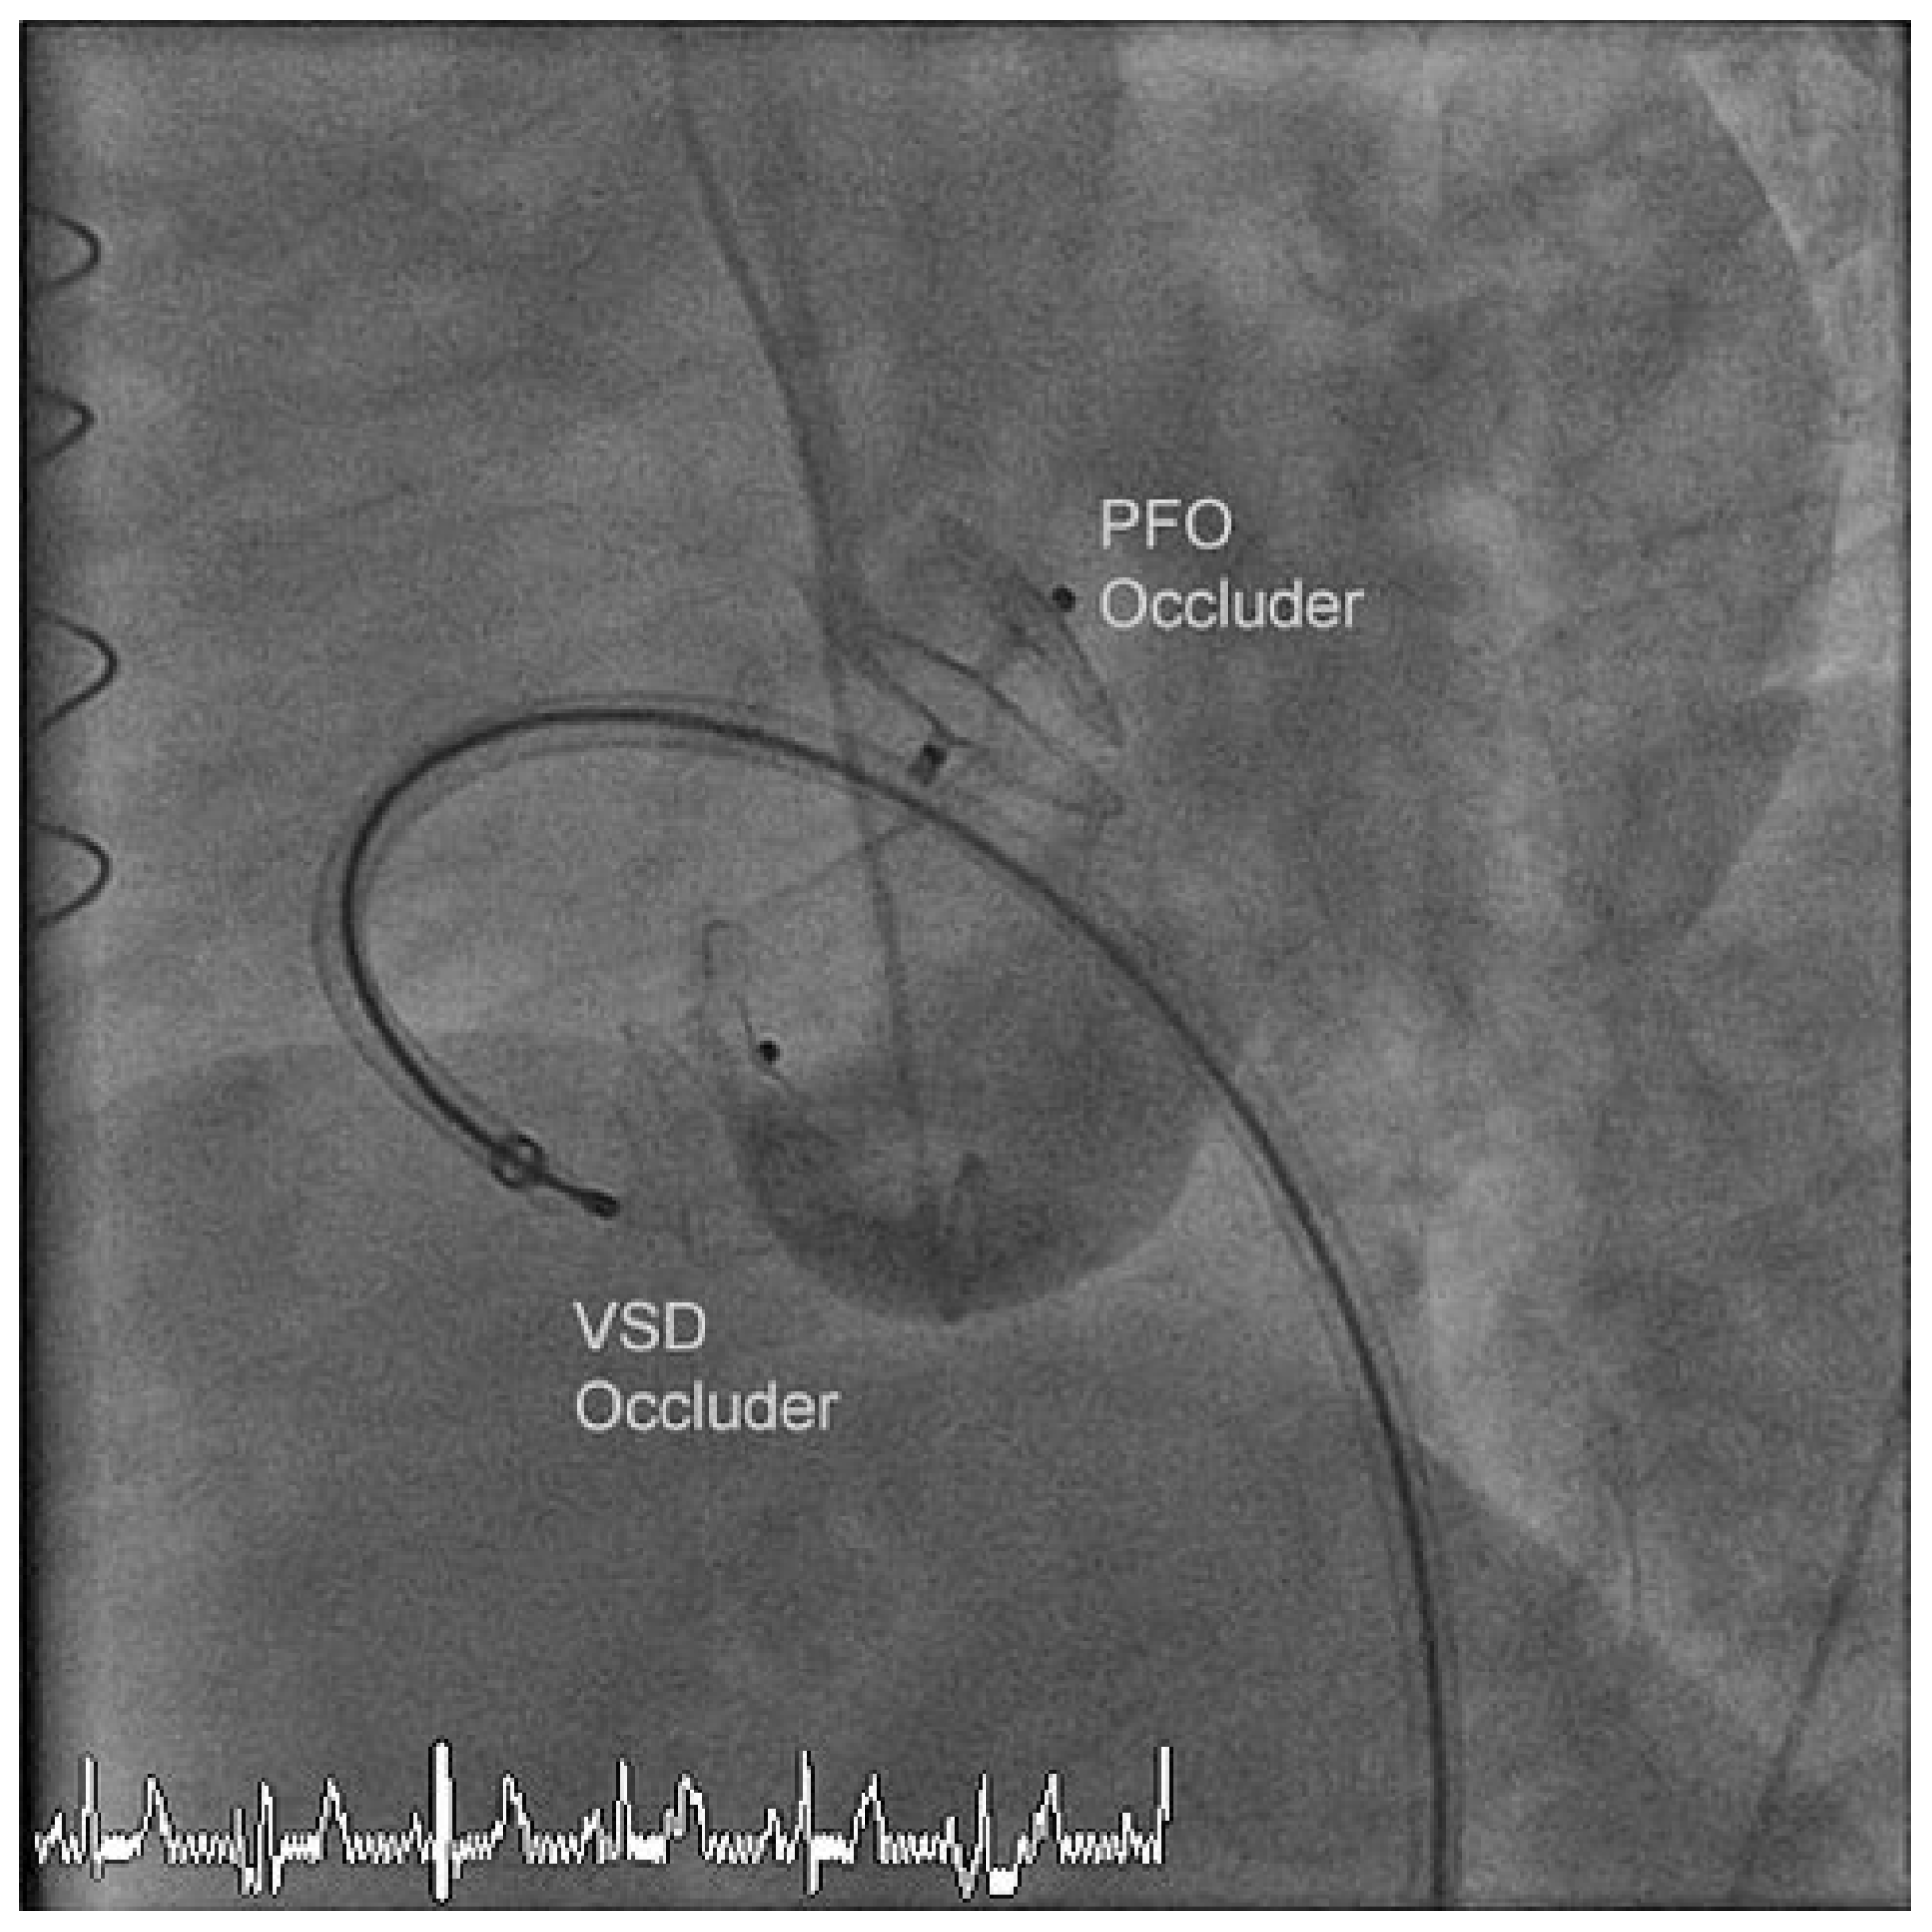

A TEE performed three months later detected a residual left-right ventricular shunt next to the VSD occluder in stable position. An additional transcatheter VSD closure was performed without sizing of the defect and a 14 × 5 mm Amplatzer Vascular Plug III (St. Jude-AGA) was aligned with the previous occluder through an 8 F TorqVue sheath inserted through the right femoral vein. He was discharged home the next day.

Three months later, a follow-up TEE demonstrated no residual left-right ventricular shunt and the two VSD occluders were aligned and in stable position (Figure 4). Nine months after the last intervention the patient reported no shortness of breath and continued dual antiplatelet therapy with acetylsalicylic acid and clopidogrel.

Figure 4. Follow-up transoesophageal echocardiogram performed six months after the initial and three months after the additional transcatheter closures of the VSD showing two devices.